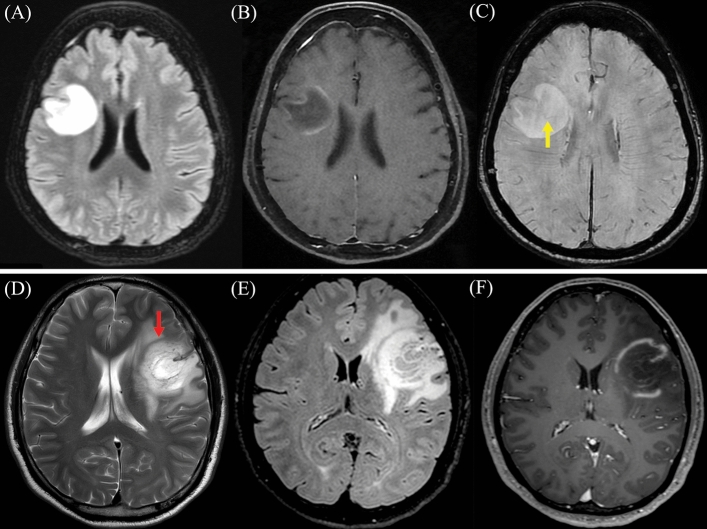

All TDL in the study demonstrated gadolinium enhancement, with open ring enhancement observed in half of the patients (50%). Upon reviewing diffusion-weighted imaging sequences, peripheral restricted diffusion, in which the area of restricted diffusion was at the lesion border, was observed in twenty-one patients (87.5%). Remarkably, we observed that the restricted diffusion area at the lesion border was typically the same area that showed gadolinium enhancement. Only 8.3% did not display restricted diffusion. Additionally, 80.8% exhibited mild perilesional edema, while 76.9% had a mild mass effect. T2W hypointense rims and the central vein sign were observed in approximately half of the patients (45% and 56.5%, respectively). Besides, brain MRI of ten patients revealed the presence of co-existing demyelinating lesions in various brain regions. Representative brain MRI from six patients within the study cohort is illustrated in Fig. 4. Representative brain MRI demonstrating the central vein sign (CVS) and the T2-weighted hypointense rim, is revealed in Fig. 5.

Figure 5.

Representative brain magnetic resonance imaging (MRI) Patient 12: (A) Axial T2-weight Fluid-Attenuated Inversion Recovery (FLAIR), (B) Axial Post-gadolinium T1-weighted imaging, and (C) Axial T2 star-weighted angiography (SWAN) reveal the presence of the central vein sign (CVS), denoted by the yellow arrow. The CVS is characterized by a hypointense thin line or small dot centrally situated within the lesion. Patient 2: (D) Axial T2-weight imaging, (E) Axial T2-weight FLAIR, and (F) Axial Post-gadolinium T1-weighted imaging exhibit the T2-weighted hypointense rim, highlighted by the red arrow. The T2W hypointense rim is defined by a thin border of T2-weighted hypointensity, contrasting with the hyperintense regions of the lesion's core and the surrounding edema.